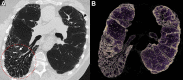

CT systems equipped with photon-counting detectors (PCDs), referred to as photon-counting CT (PCCT), are beginning to change imaging in several subspecialties, such as cardiac, vascular, thoracic, and musculoskeletal radiology. Evidence has been building in the literature underpinning the many advantages of PCCT for different clinical applications. These benefits derive from the distinct features of PCDs, which are made of semiconductor materials capable of converting photons directly into electric signal. PCCT advancements include, among the most important, improved spatial resolution, noise reduction, and spectral properties. PCCT spatial resolution on the order of 0.25 mm allows for the improved visualization of small structures (eg, small vessels, arterial walls, distal bronchi, and bone trabeculations) and their pathologies, as well as the identification of previously undetectable anomalies. In addition, blooming artifacts from calcifications, stents, and other dense structures are reduced. The benefits of the spectral capabilities of PCCT are broad and include reducing radiation and contrast material dose for patients. In addition, multiple types of information can be extracted from a single data set (ie, multiparametric imaging), including quantitative data often regarded as surrogates of functional information (eg, lung perfusion). PCCT also allows for a novel type of CT imaging, K-edge imaging. This technique, combined with new contrast materials specifically designed for this modality, opens the door to new applications for imaging in the future.